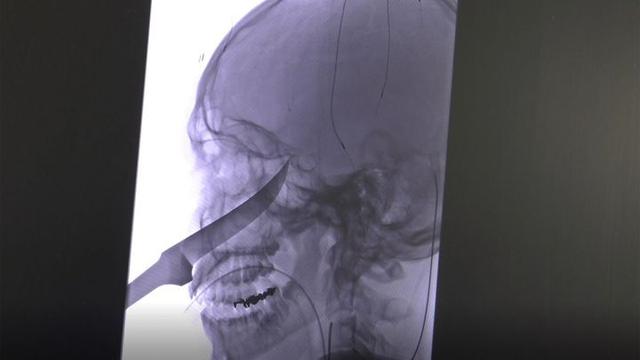

Liputan6.com, Washington DC - Seorang dokter di Kansas Amerika Serikat baru-baru ini menolong seorang anak berusia 15 tahun dengan pisau sepanjang 25,4 cm bersarang di otaknya. Remaja itu bernama Eli Gregg, yang tengah bermain di luar rumah pada Sabtu, 15 Juni 2019 saat ibunya mendengar dia berteriak keras.

Rupanya, Eli sedang memegang pisau ketika ia terjatuh. Tanpa sengaja, logam tajam itu menembus wajahnya, dan tertanam di tengkoraknya. Setelah diperiksa dokter, akhirnya diketahui ujung pisau berhenti tepat di arteri karotisnya --sepasang pembuluh darah yang yang mengantarkan darah ke otak dan kepala.

Eli dilarikan dengan ambulans ke rumah sakit anak-anak terdekat. Saat itu, para dokter khawatir posisi pisau yang berbahaya di sebelah arteri karotis membuatnya berisiko terserang stroke atau kerusakan serius lain.

Ia kemudian dibawa ke rumah sakit University of Kansas Health. Dengan sigap, Dr. Koji Ebersole membantu mengeluarkan pisau itu dari kepalanya.

Saat itu, Ebersole dan timnya harus mengendalikan pendarahan di area kepala itu dengan piranti khusus. Sebelum akhirnya mereka dapat benar-benar menghilangkan bilah pisau dari wajah Eli Gregg, menurut Fox News.

Para ahli bedah melaporkan bahwa mereka harus menggunakan catok untuk menggenggam pisau itu, bukan dengan tangan mereka. Prosedur medis itu berhasil, dan Eli kemudian berada pada tahap pemulihan.